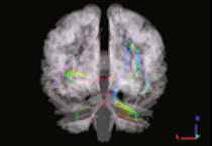

«Изменения коннектома головного мозга у пациентов с детским церебральным параличом в поздней резидуальной стадии при транслингвальной нейростимуляции». Обобщена МР-семиотика структурных и функциональных изменений головного мозга у детей со спастической диплегией. У детей с ДЦП в поздней резидуальной стадии преобладает снижение коннективности между компонентами сети выявления значимости и корой лобно-теменной области, компоненты которой также структурно связаны с компонентами сенсомоторной сети. При выполнении коннектометрического анализа трактов после ТЛНС (основная группа) выявлено повышение фракционной анизотропии более чем на 20 % (p < 0,001) в передней спайке (47 % от общего количества волокон), правом нижнем лобно-затылочном пучке (13 % волокон), левой поясной извилине (10 % волокон), правой зрительной лучистости (6,7 % волокон), мозолистом теле (6 % волокон), правой поясной извилине (1,3 %) (рисунок).

| Графическое представление результатов межгруппового статистического анализа: 2D-реконструкция проводящих путей белого вещества головного мозга с повышением ФА после ТЛНС в аксиальной (а), сагиттальной (б) и корональной (в) плоскостях. Показаны проводящие пути и часть их волокон, которые повысили ФА более чем на 20 % после комплексной реабилитации | ||

При выполнении коннектометрического анализа трактов после стандартной двигательной реабилитации (группа сравнении) статистически значимого повышения фракционной анизотропии (более чем на 20 %) не выявлено. При проведении диффузионной МРТ у детей с ДЦП в поздней резидуальной стадии выявлено статистически значимое снижение фракционной анизотропии в трактах белого вещества головного мозга, что свидетельствует о нарушении общих процессов миелинизации и, следовательно, скорости проведения нервных импульсов по их аксонам. Выявлены структурные и функциональные изменения головного мозга у пациентов с ДЦП после ТЛНС, которые свидетельствуют об усилении активации процессов нейропластичности.